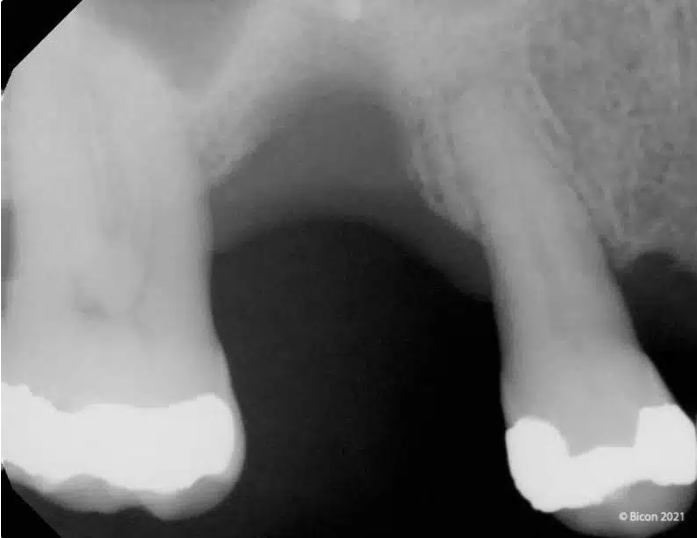

Caso Bicon: Seguimiento radiográfico de siete años de un implante Bicon SHORT® de 6,0 x 5,0 mm con un pilar de elevación de seno y una corona de pilar integrada (IAC)

Seguimiento radiográfico de siete años de un implante Bicon SHORT® de 6,0 x 5,0 mm con un pilar de elevación de seno y una corona de pilar integrada (IAC)

Presentamos el caso de un paciente masculino de 69 años, en el que se realizó la extracción dental seguida de la colocación de un implante Bicon SHORT® de 6,0 x 5,0 mm con pilar de elevación de seno.

El caso se restauró con una corona de pilar integrado (IAC) de 20 mm de longitud y ha sido seguido durante 84 meses.

Este caso destaca no solo por la estabilidad a largo plazo del implante corto, sino también por mostrar de forma radiográfica la aplicación de la Ley de Wolff: el hueso se adapta y se refuerza en respuesta a la carga funcional.